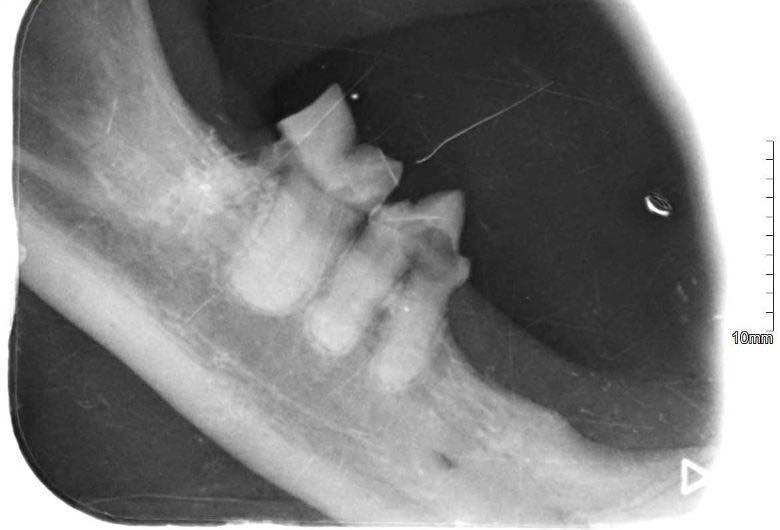

Zaczęło się od trudności z jedzeniem 🍽️, zgłoszonych przez tymczasową mamę, które skłoniły nas do dokładniejszej kontroli. Podczas wizyty weterynaryjnej okazało się, że zęby Loli wymagają pilnej interwencji. Została więc skierowana na zabieg stomatologiczny 🦷, w trakcie którego wykonano RTG jamy ustnej. Badanie wykazało sporo zmian – aż 8 zębów musiało zostać usuniętych.